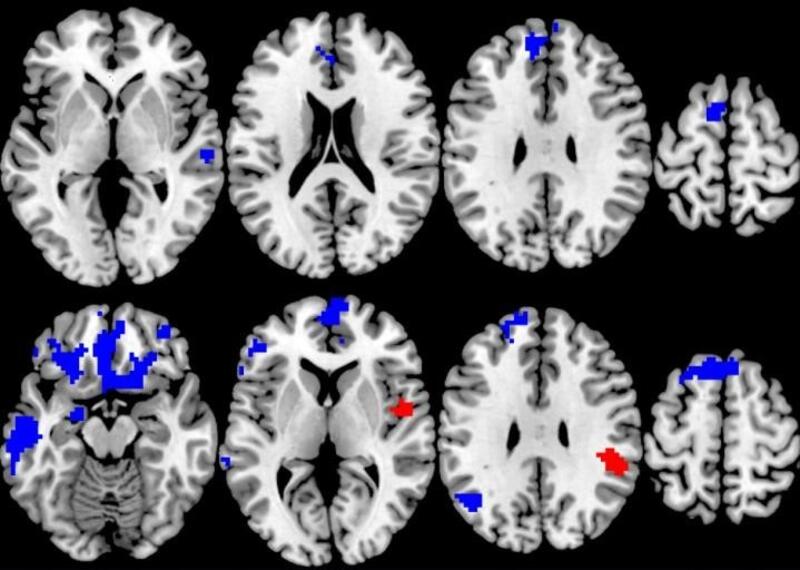

Pero cuando los investigadores analizaron los escáneres cerebrales realizados antes de que los pacientes comenzaran la terapia y los relacionaron con la respuesta al tratamiento individual, encontraron patrones sorprendentes.

Los escáneres cerebrales se tomaron mientras los pacientes realizaban una simple tarea cognitiva y respondían a una pequeña recompensa monetaria si hacían la tarea correctamente.

Los que empezaron con más activación en los circuitos cerebrales para procesar las demandas cognitivas y la recompensa durante las pruebas tenían más probabilidades de responder a la TCC, pero los que empezaron con menos activación en esas mismas áreas durante las mismas pruebas tenían más probabilidades de responder bien a la TSM.

"Encontramos que la forma de terapia más específica para el TOC, la que se basa en la exposición al foco de la obsesión y la compulsión, era mejor para aliviar los síntomas, lo que en sí mismo es un valioso hallazgo de esta comparación aleatoria cara a cara de dos opciones de tratamiento. Pero cuando observamos el cerebro para ver qué había detrás de esa respuesta, encontramos que cuanto más fuerza tenían los pacientes en ciertas áreas del cerebro, más posibilidades había de responder a la TCC basada en la exposición", explica la líder del estudio, Stephan Taylor.